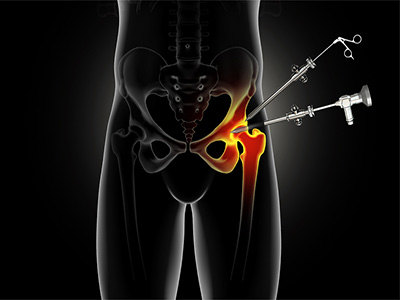

Hip Arthroscopy

Hip Arthroscopy Anterior Hip Replacement